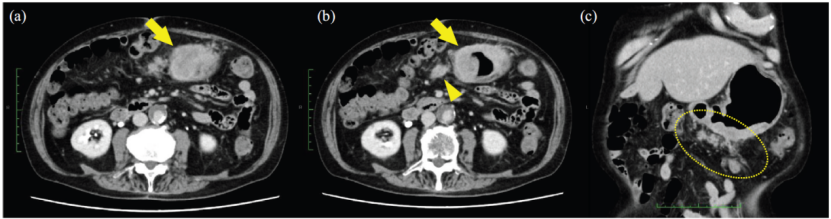

影像学检查: CT示胃下部胃壁不均匀强化,伴胃周淋巴结转移及大网膜种植转移可能(图2)。

图2. 诊断时的腹部CT检查结果。腹部CT (a-c) 显示胃下部胃壁不均匀强化(箭头),胃周淋巴结转移(三角箭头),以及大网膜种植转移可能(虚线圈)